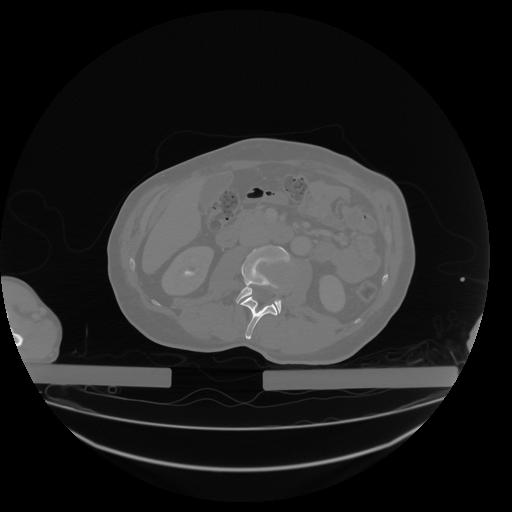

34 CUERPO,CE,Vol,1.0,CUERPO,,